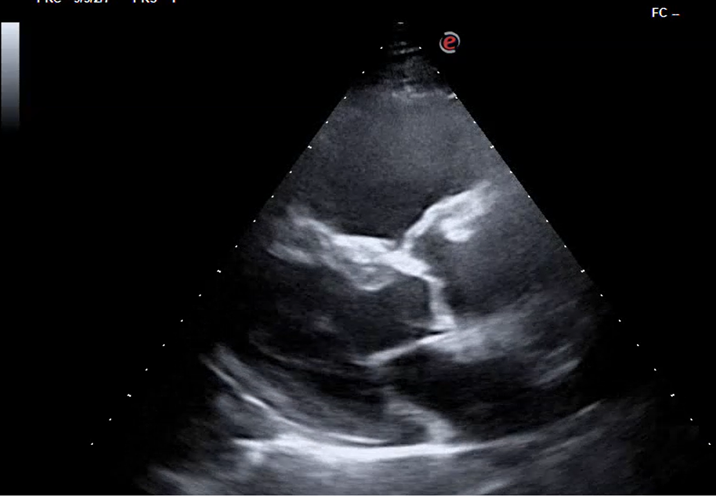

Hombre de 84 años con disnea progresiva de 6 meses de evolución: neoplasia pulmonar estadio IV con metástasis óseas.